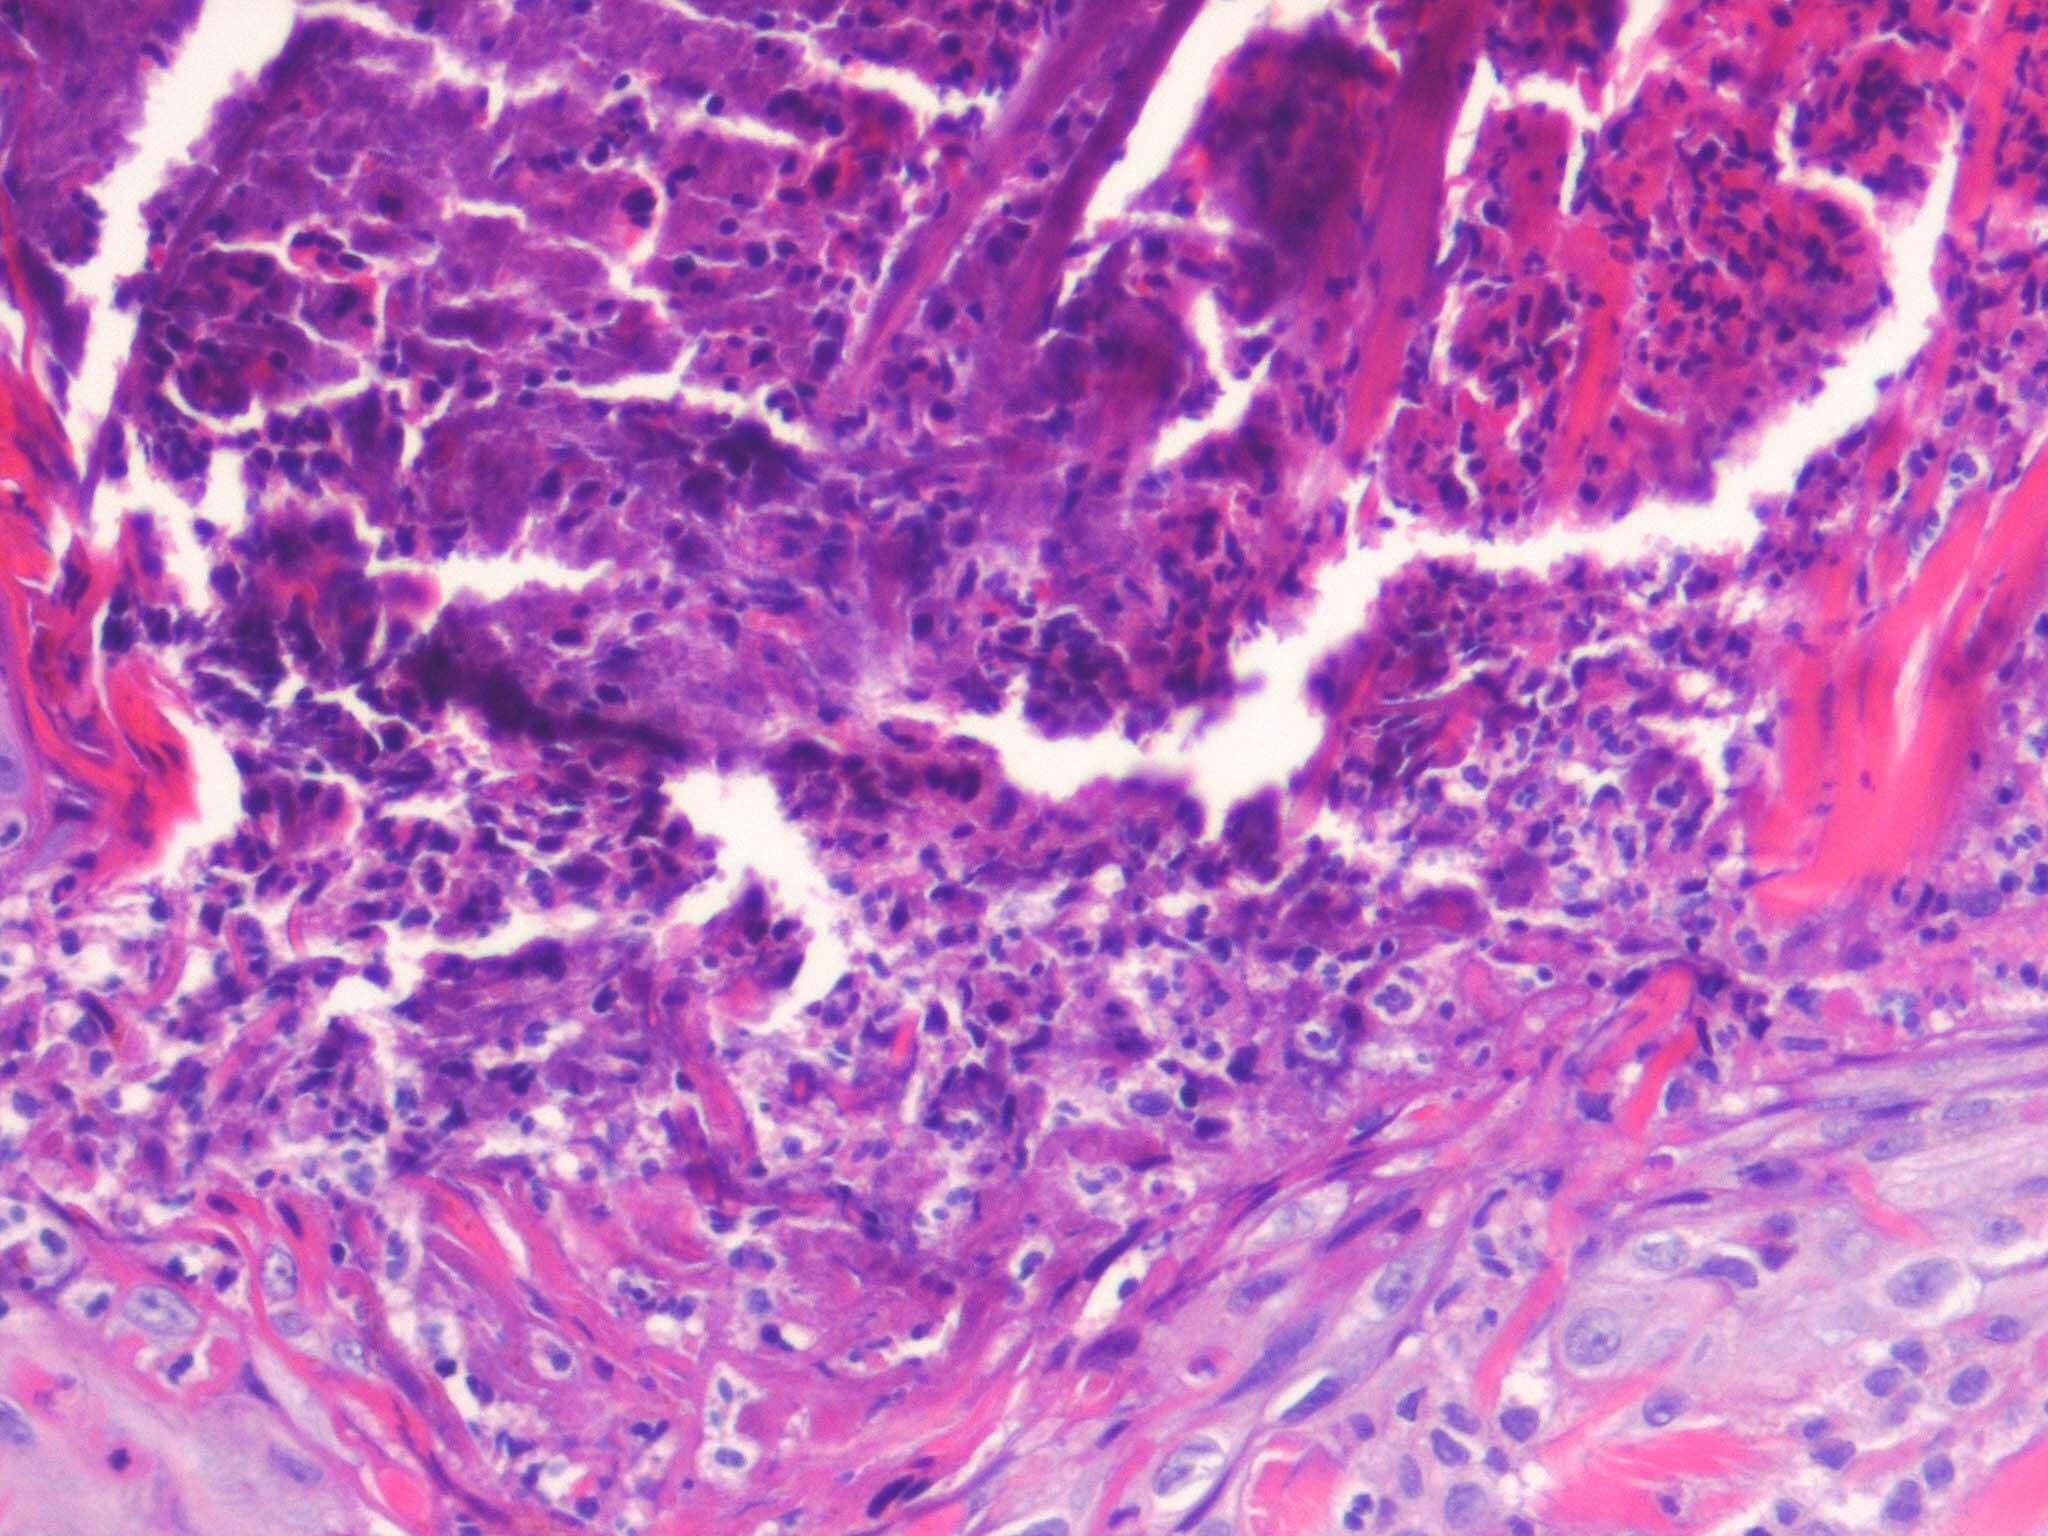

The histology varies with the stage of the reactive perforating collagenosis. Early lesions show epidermal hyperplasia associated with underlying degenerate basophilic collagen fibers. In established lesions, a cup-shaped depression of the epidermis associated with a keratin plug containing parakeratosis, inflammatory debris and collagen fibers can be seen.

Vertically orientated basophilic collagen fibers are seen in the underlying dermis, with focal extrusion through the epidermis

The epidermis is atrophic and may show ulceration. However, at the edges of the cup-shaped invagination, the epidermis is hyperplastic. Additionally, a mild perivascular lymphohistiocytic infiltrate can be seen.